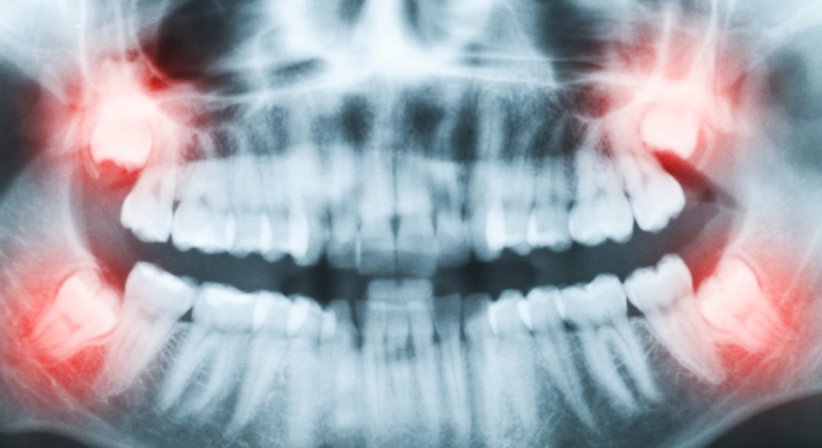

Bei vielen Menschen tritt der Weisheitszahn aufgrund von Platzmangel im Gebiss nur unvollständig durch. Dieser teilweise Durchbruch wird als Teilretention bezeichnet.

Da es bei teilretinierten Zähnen häufig zu lokalen Entzündungen mit Schwellungen bis hin zu Abszessen kommen kann, empfiehlt sich die Entfernung der betroffenen Zähne.